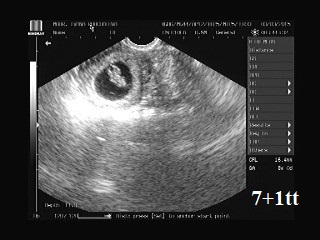

Posílám fotečku z dnešní kontroly 7+1tt :-), nevolnosti trvaly 2 týdny a najednou se po nich slehla zem :-D takže až na neustálou ospalost se nám vede dobře :-)